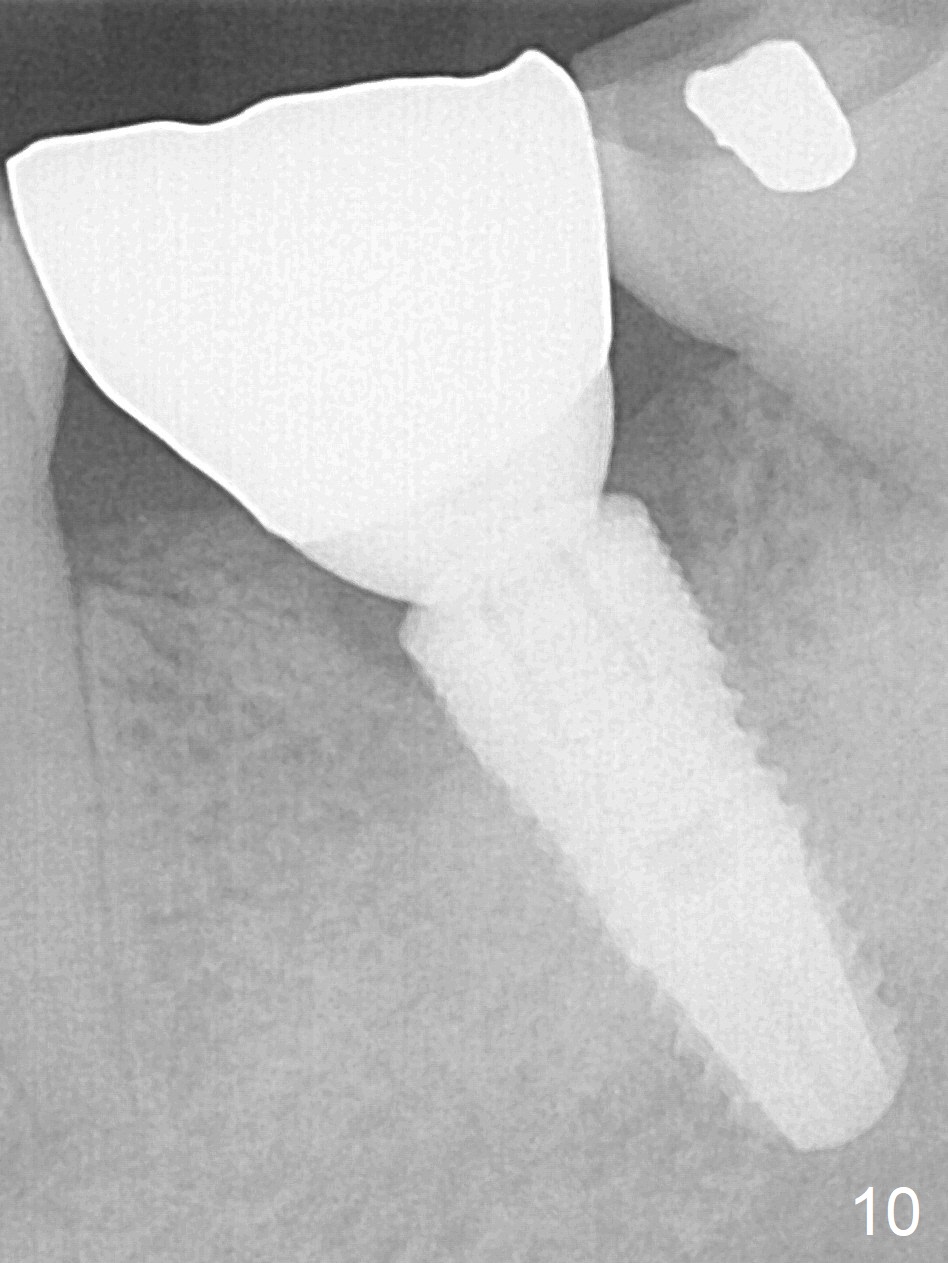

It appears that the loss of the provisional in this case is due to untightening the abutment. The most secure method to fix the abutment/implant in place is to apply setting acrylic to the undercut without taking it out immediately. This is called provisional without cement (1 2 3 4 5). Bone density increases in the peri-implant space 16 months post cementation (Fig.10) and continues to increase 2 years 8 months post cementation (Fig.11).